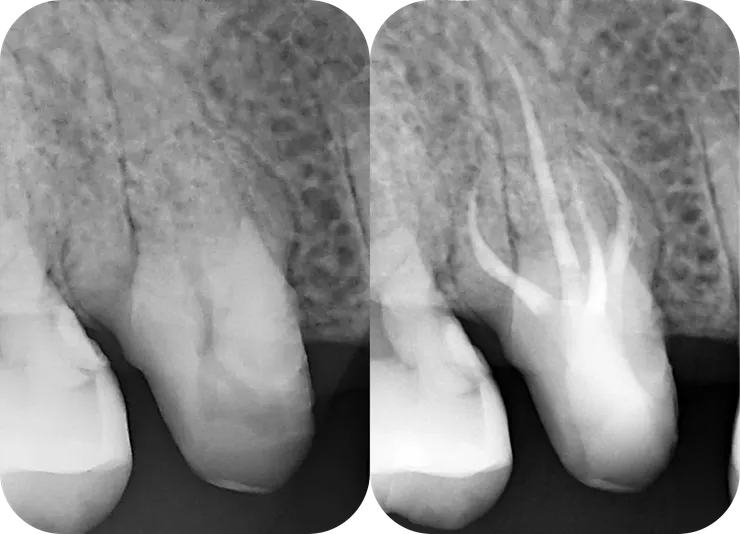

然後就在第三個 appointment 順利 RCF.DB orifice 上方也是類似的情況,有一區蓋過來的 dentin. 但因為 DB 洞明顯的比 MB2 洞大多了,所以我沒多加處理。就這樣試著把 file 督進去......

可以看到為了完成這邪惡的 DB canal, pericervical dentin & danger zone 的齒質都各犧牲了一些,而通常 pericervical dentin 的犧牲會多一些......

總結這兩顆牙較具挑戰的四個 canals, 單看個別的 canal 彎曲情形,我給它們的難度排名如圖中的綠色編號。DB orifice 上方也是類似的情況,有一區蓋過來的 dentin. 但因為 DB 洞明顯的比 MB2 洞大多了,所以我沒多加處理。就這樣試著把 file 督進去......

因為我覺得,就算 NiTi rotary 再怎麼軟,因為越上端處 file 越粗 (任何 taper 大於 .04 的系統),過彎能力就會越差,風險越高!

因此若是 canal 的第一個彎越大,以及過彎之後底下的 canal 越長,就越困難。

然而為何看起來比較困難的

第一名 26 DB (24mm, PTG F1)

做起來卻感覺比

第二名的 16 MB2 (16.5mm, PTG F1)

輕鬆許多呢?